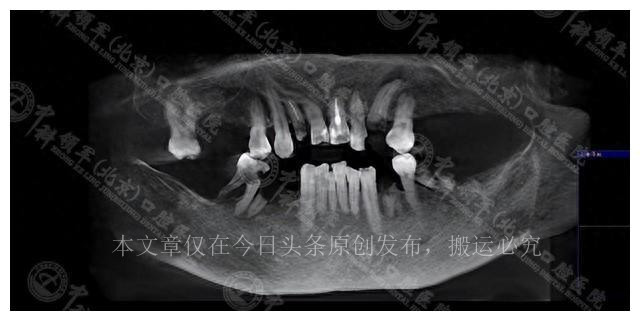

李女士的牙齿问题并非小事,她的口腔健康直接关系到她的生活质量。她有11颗牙齿缺失,其中上半口缺5颗,下半口缺6颗,而剩余的牙齿已经松动,牙槽骨也有轻度吸收。

在医生的建议下,李女士面临两种选择。首先是保守治疗方案,它包括拔除6

颗有问题的牙齿,进行根管治疗,种植4颗缺失的牙齿,并对2颗需要修复的牙齿进行补牙,最后对上前牙区进行冠桥修复。这个方案虽然需要较多的复诊次数,总体费用为5.5万元,但保留了一部分原有的好牙,显然是一种相对保守的治疗方式。